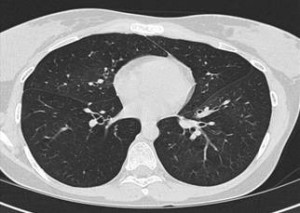

Expiratory (top figure) and Inspiratory (bottom figure) cuts from Chest CT are shown below:

The combination of obstructive pattern on PFT with no bronchodilator effect associated with air trapping in a mosaic pattern in the expiratory CT cuts more then the inspiratory cuts is almost pathognomonic for this diagnosis.